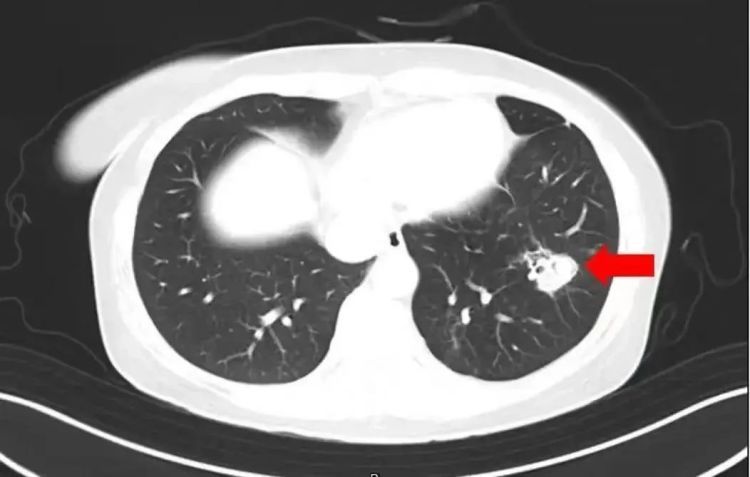

为进一步确诊病情,医生为她进行纤维支气管镜检查及肺泡灌洗液病原体检测,果然发现气道壁上有大量白色菌斑,化验后确认是曲霉菌。